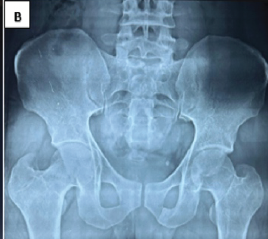

Arthroscopic-Assisted Removal of Incarcerated Fragment following Manual Reduction of Posterior Hip Dislocation in Acute Polytrauma Patient: A Case Report